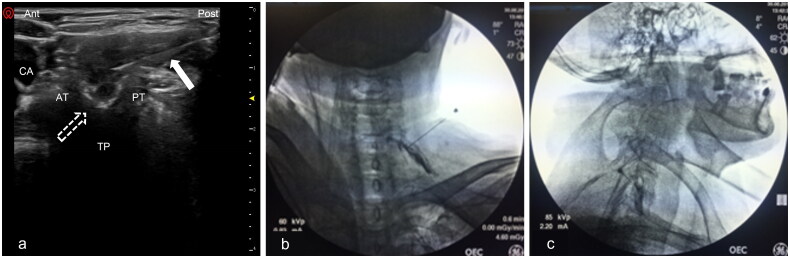

Cervical interlaminar epidural injection: lateral view (A) and contralateral oblique view (B) showing ventral epidural contrast spread. White arrows indicate the Tuohy needle position.